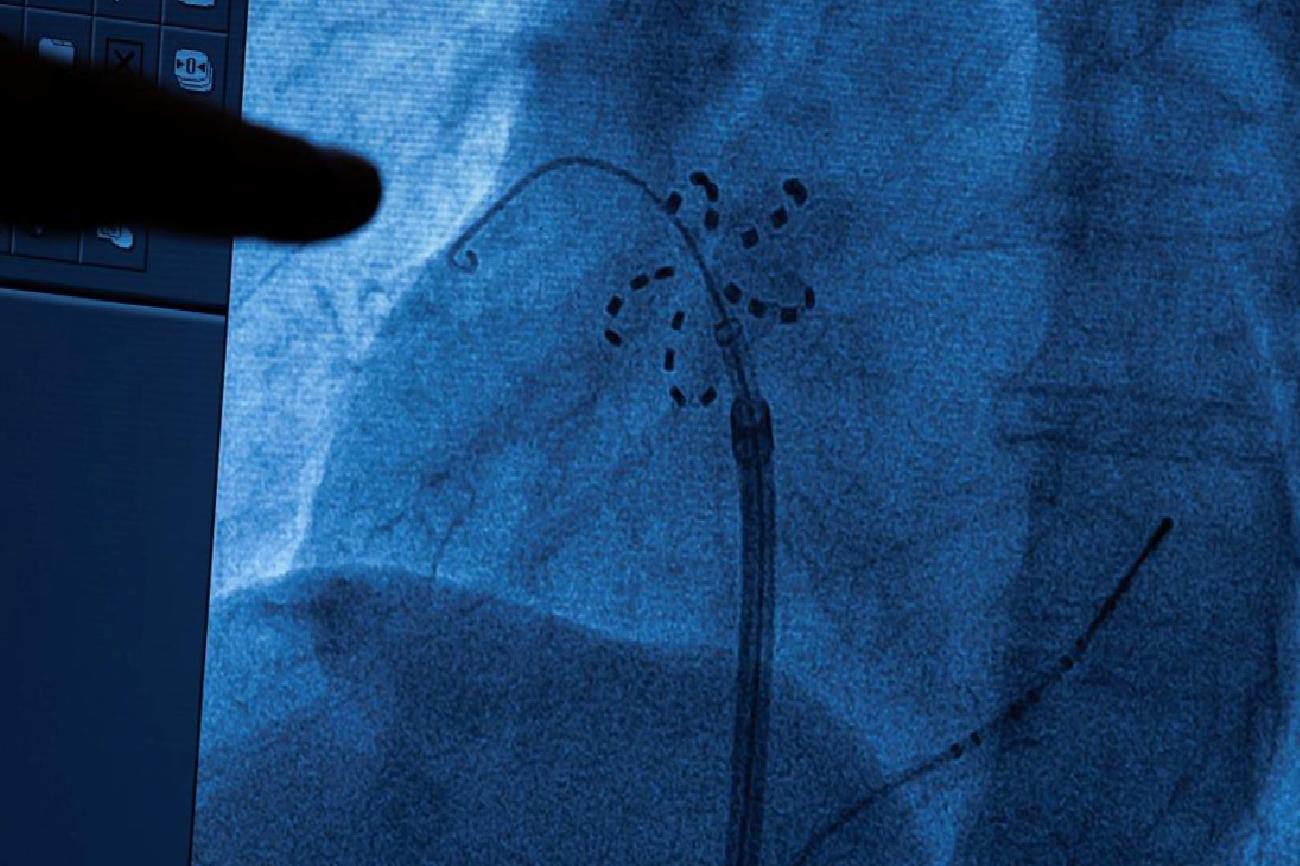

Geçmişte radyo frekans ve kriyoablasyon gibi geleneksel ablasyon teknikleri kullanılmış olsa da bu yöntemler kalbin çevresindeki dokulara zarar verebiliyor ve nadiren de olsa akciğer damarlarında daralma, yemek borusu ve solunum sinirinin hasarlanması gibi ciddi komplikasyon riskleri taşıyordu. PFA ile bu önemli riskler minimuma iniyor. Yöntem, kasıktan damar yoluyla ilerletilen kateterin ucundaki elektrotla problemli dokulara yüksek frekanslı elektrik dalgası gönderilmesiyle dokuların elektriksel aktivasyonunun ortadan kaldırılmasını sağlıyor ve ritim bozukluğu tedavi ediliyor.